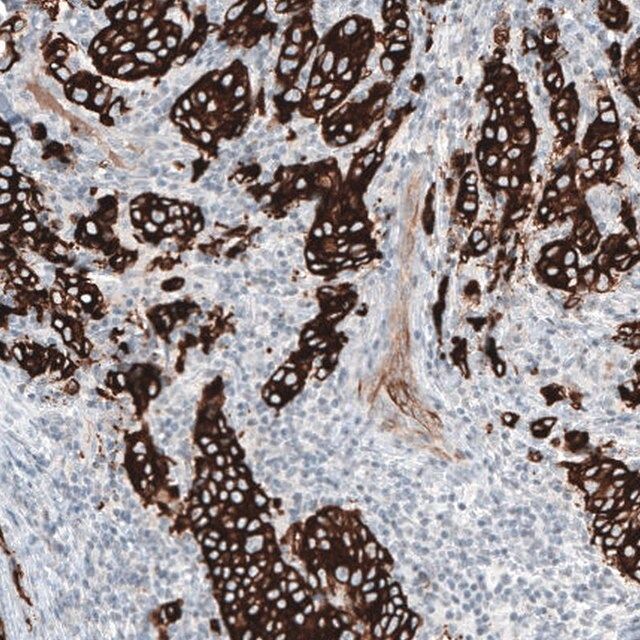

All Prestige Antibodies Powered by Atlas Antibodies are developed and validated by the Human Protein Atlas (HPA) project (www.proteinatlas.org)and as a result, are supported by the most extensive characterization in the industry. The Human Protein Atlas project can be subdivided into three efforts: Human Tissue Atlas, Cancer Atlas, and Human Cell Atlas. The antibodies that have been generated in support of the Tissue and Cancer Atlas projects have been tested by immunohistochemistry against hundreds of normal and disease tissues and through the recent efforts of the Human Cell Atlas project, many have been characterized by immunofluorescence to map the human proteome not only at the tissue level but now at the subcellular level. These images and the collecation of this vast data set can be viewed on the Human Protein Atlas (HPA) site by clicking on the Image Gallery link. To view these protocols and other useful information about Prestige Antibodies and the HPA, visit sigma.com/prestige.

- IHC tissue array of 44 normal human tissues and 20 of the most common cancer type tissues.

| technique(s) | immunohistochemistry: 1:500-1:1000 western blot: 1 μg/mL |